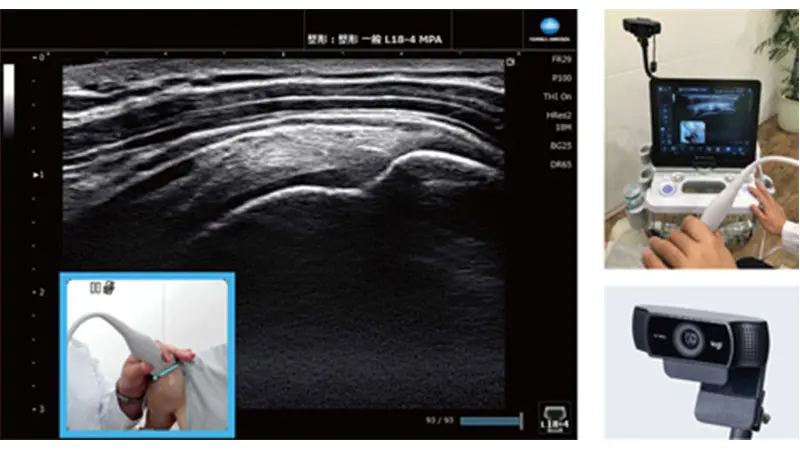

超音波画像とカメラ画像を同時表示

Camera Link

カメラで撮影した映像を、診断中の超音波画像に重ねて表示します。表示した画像は、静止画と動画で記録でき、動画記録時は音声情報も保存できます。超音波画像と一緒に、検査状況がリアリティをもって記録されるため、後から検査状態を確認する際や、他者への説明に便利です。

*専用のカメラ・その他付属品はオプション品です。